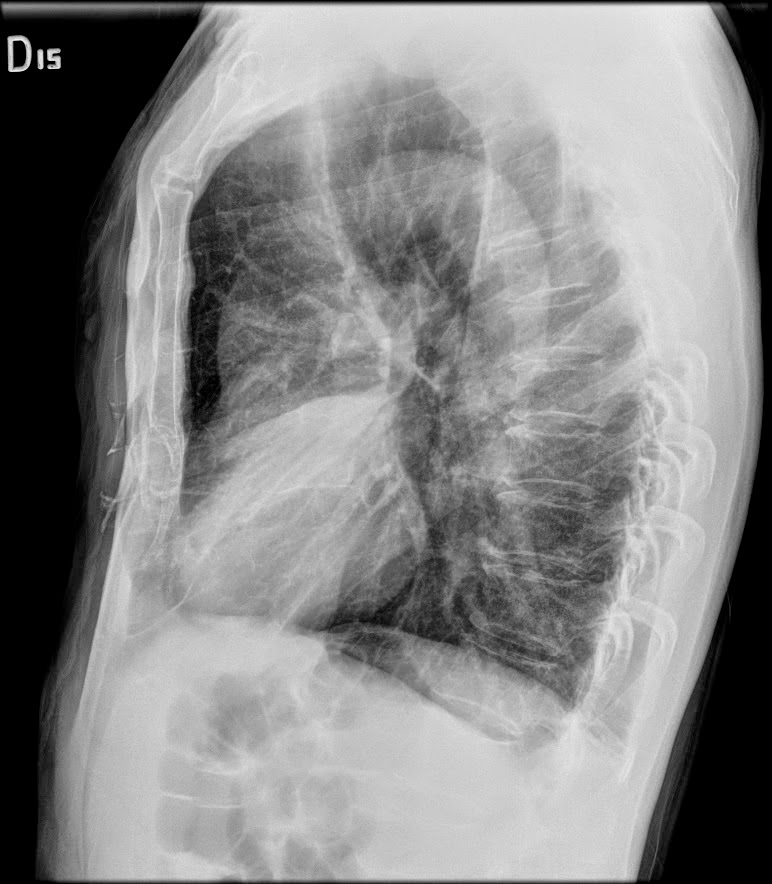

Caso interesante #6

Otro casito de un tórax para localizar la consolidación